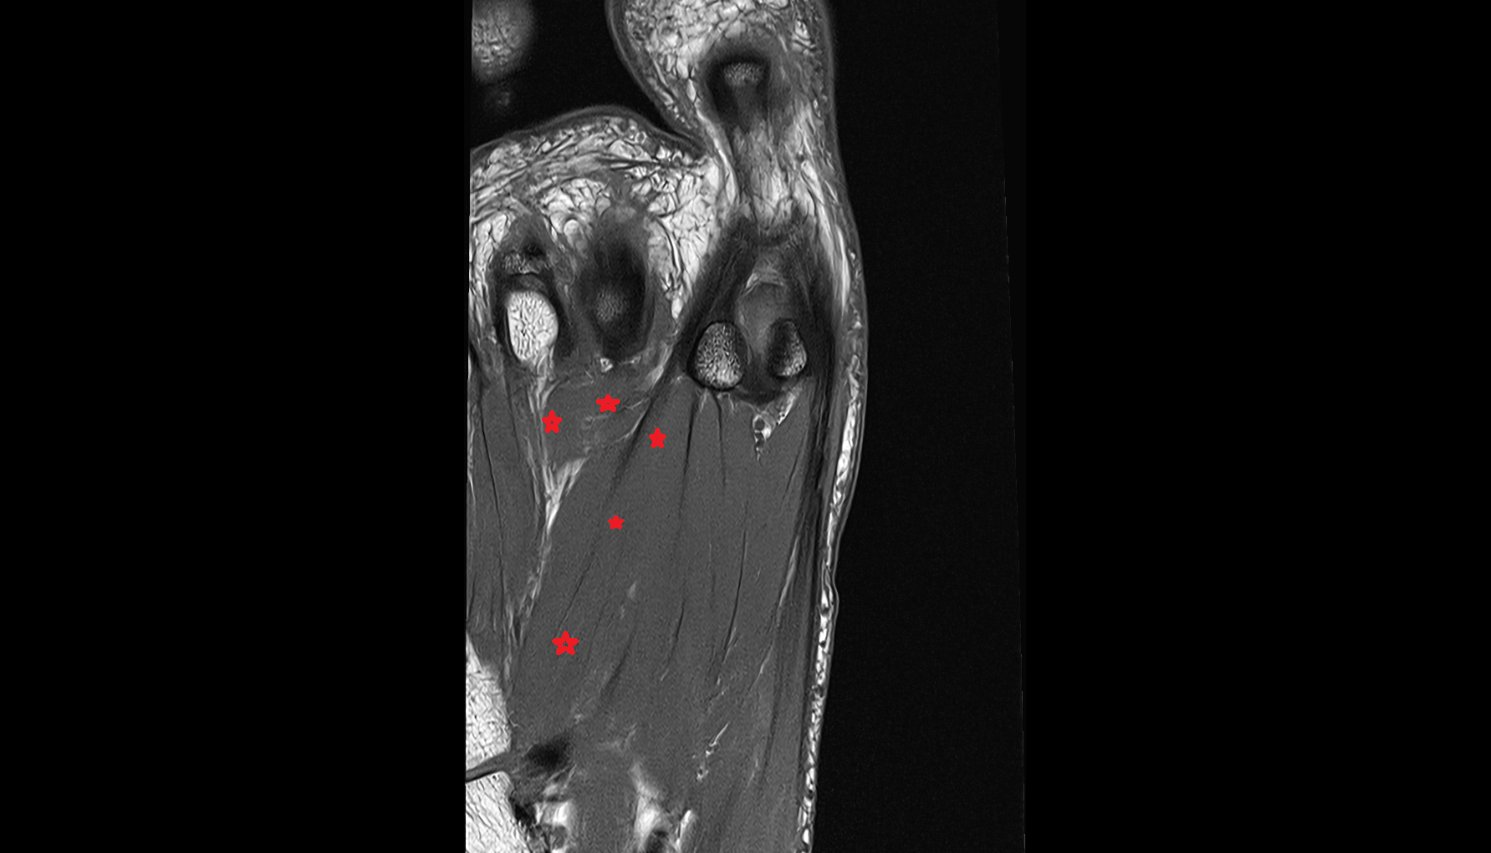

- Plantar aponeurosis